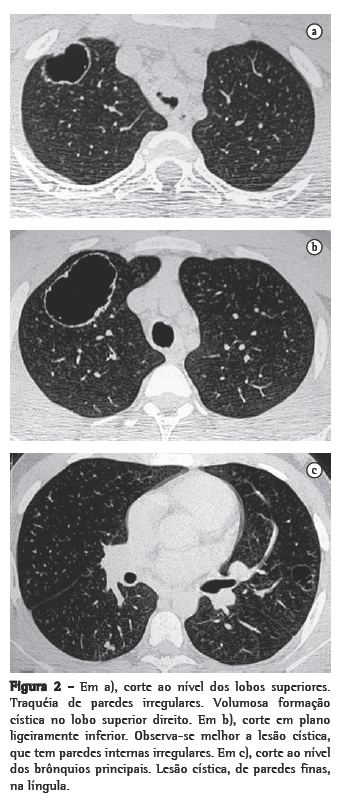

Nos 8 casos foram observadas na TC formações polipóides na traquéia. Em 1 deles, identificou-se também uma lesão em brônquio principal. Sete pacientes mostravam comprometimento do parênquima pulmonar. Em todos foram observadas lesões nodulares escavadas, com contornos internos irregulares, e paredes de espessuras variadas, com aspecto multilobulado em 6 casos, e com confluência das lesões em 5 deles (Figuras 1 a 5). Nódulos sólidos foram vistos em 6 pacientes, Em apenas 1 dos casos foram vistos níveis líquidos. As lesões predominaram nas bases em 3 pacientes, nos terços médios em 2, e em 2 não havia predomínio de distribuição. Em 1 dos pacientes, foi observada associação com massa, e em outro, com consolidação. Neste último paciente (Figura 5) foi constatada degeneração maligna em múltiplas lesões. Sinais de aprisionamento aéreo também foram observados em 1 caso. Em nenhum deles detectou-se linfonodomegalia ou derrame pleural.

A degeneração maligna para carcinoma de células escamosas é relatada entre 1% e 10% dos casos de PLTB,(3,4) em geral ocorrendo após a irradiação ou quimioterapia com bleomicina, ou em pacientes com história de tabagismo.(1,6) Pode acontecer na infância ou mesmo décadas após o diagnóstico de papilomas benignos.(4) Na maior parte dos casos, ocorre em pacientes com disseminação prévia da doença para a árvore traqueobrônquica. Raramente pode ocorrer na forma laríngea da doença.(2,5) Em 1 dos casos estudados, houve degeneração maligna, constatada em biópsias realizadas em três diferentes lesões.